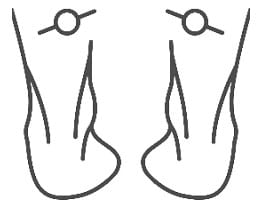

1.İçe Basma (Aşırı Pronasyon)

Ayağın iç kısmının yere fazla temas etmesidir.

- Topuk yere bastığında ayak içe doğru döner.

- Ayakkabıların iç kenarı daha hızlı aşınır.

- Düz tabanlık, diz ve bel ağrılarıyla ilişkilidir.

2.Dışa Basma (Supinasyon)

Ayağın dış kenarına ağırlığın fazla verilmesidir.

- Ayağın iç tarafı yere yeterince temas etmez.

- Ayakkabıların dış tabanı daha çabuk yıpranır.

- Baldır kaslarında gerginlik ve ayak bileği burkulmaları sık görülür.